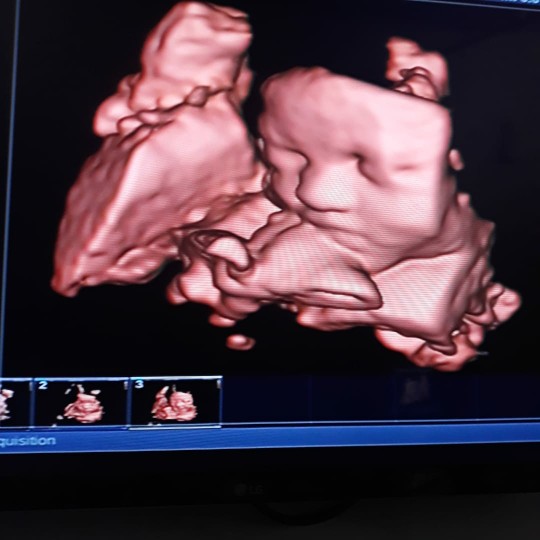

Mahal juga ya bun 😥 tadi aku ke puskes nanya usg 4D ga bisa pake bpjs katanya padahal aku kepengen banget bun😢